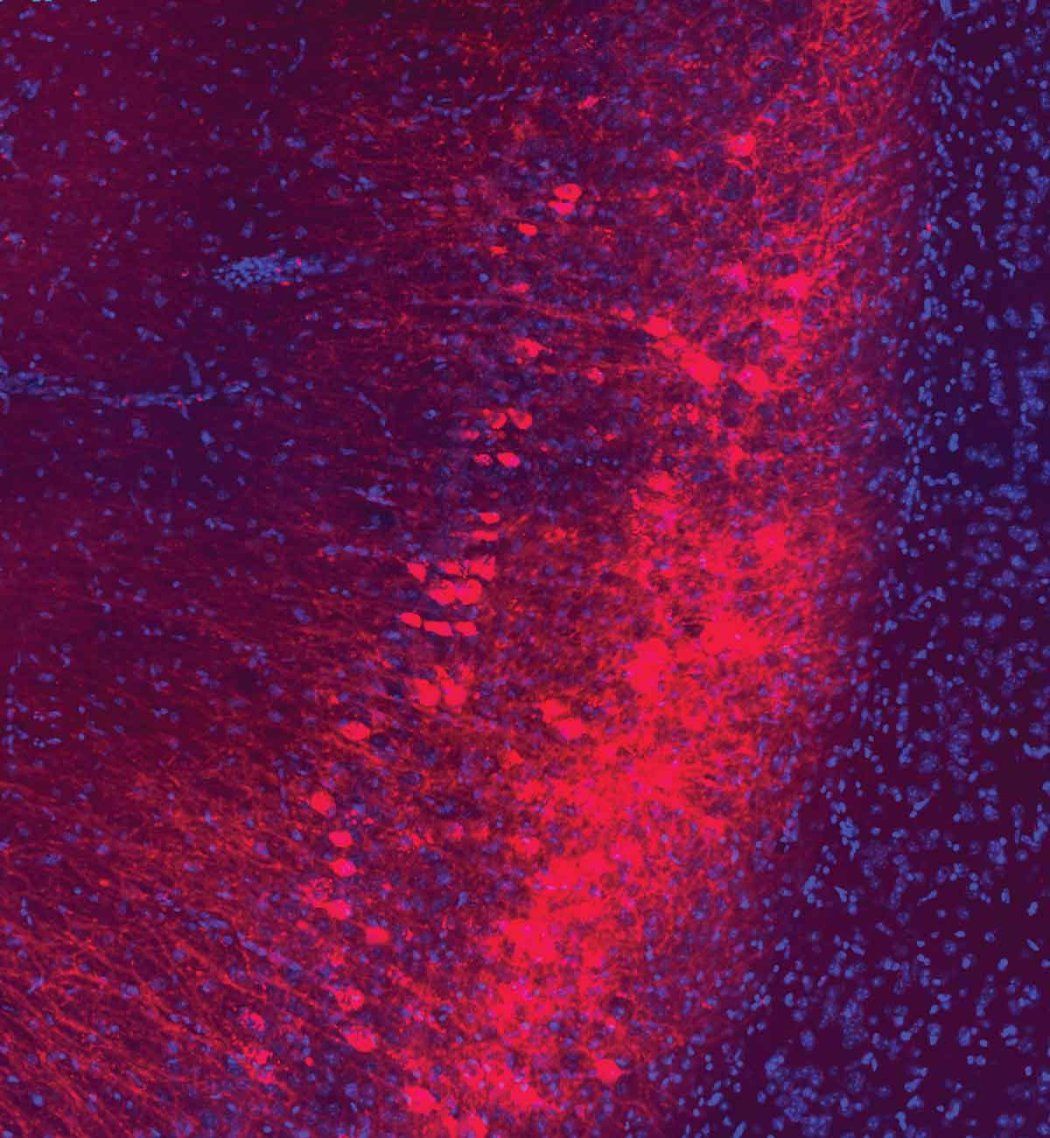

The researchers looked at a brain region called the amygdala, which helps to evaluate how risky it may be to seek a reward.

Xia looked at brain recordings of the mice who chose the sweet water. Their amygdala was communicating with a nearby brain region called the hippocampus that remembers and predicts.

She saw a different pattern in the mice that could not decide whether to drink the plain or sweetened water. In those mice, the conversation between the two brain areas sputtered.